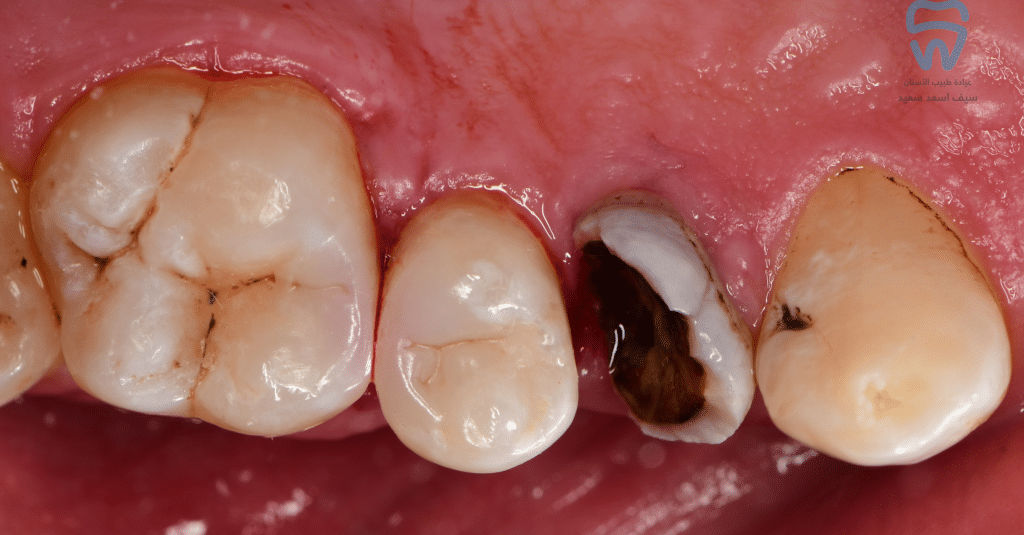

Initial situation

Caries excavation and cavity design